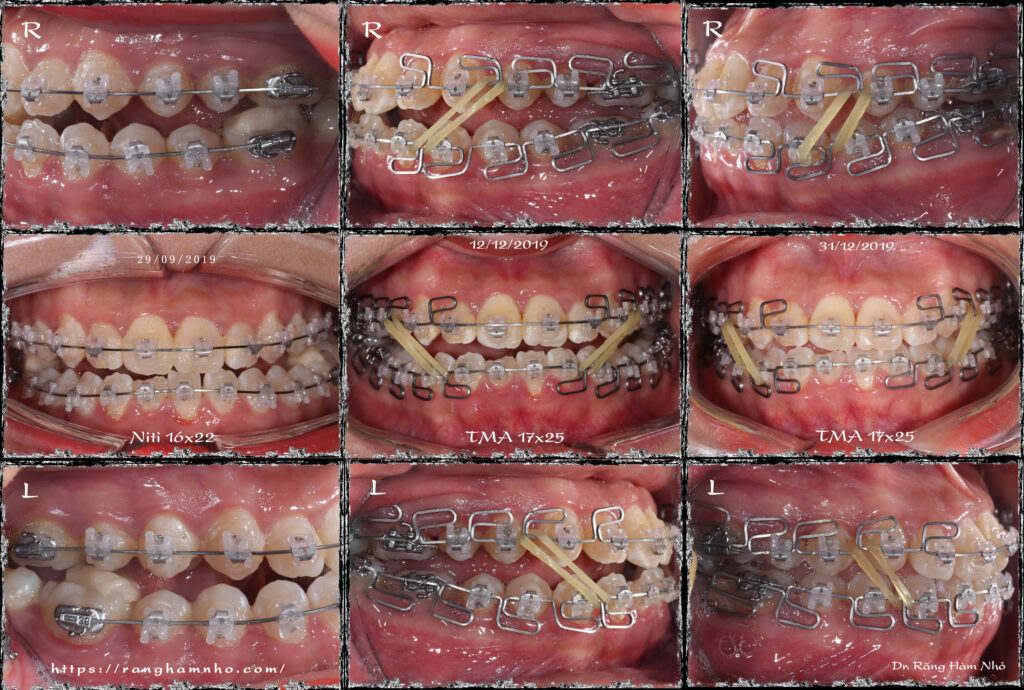

Một case sai khớp cắn hạng III góc đóng, với chen chúc cắn kéo nhiều răng. Giai đoạn san bằng và sắp đều đã được hoàn thiện trước đó. Dr Răng Hàm Nhỏ tiếp nhận và bẻ MEAW trên dây TMA 17×25 kết hợp thun 1/4 hạng III ngắn 6.5Oz trong 6 tháng. Giải quyết được hở khớp vùng răng hàm, lồng khớp hai hàm về tối ưu. Tinh chỉnh khớp cắn, duy trì và tháo niềng.